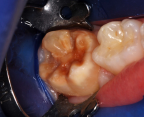

A 9-year-old boy had a partially erupted mandibular first molar with much hypocalcification of the occlusal surface and a large caries lesion involving the occlusal and buccal surfaces (Figure 1). The patient complained of continuing sensitivity to cold stimulus and air inspiration. Because the tooth was only partially erupted, consideration for stainless steel crown full coverage had to be delayed. As an interim repair, it was decided to debride the carious tooth substance and place a light-hardened calcium silicate/mineral trioxide aggregate (MTA) liner, followed by a bonded restoration. After inferior alveolar block anesthetic injection and cotton roll isolation, cavity outline form was cut using a high-speed, water-cooled, medium-grit cylindrical diamond bur (Figure 2). Insufficient eruption precluded use of a rubber dam. A large, round bur at slow speed was used to debride the carious enamel and dentin. The prepared surfaces were swabbed for two 60-second applications of a 5% glutaraldehyde/HEMA solution for desensitization and disinfection of the preparation.6,7 Cavity liner was then injected and spread over the deepest sections of the cavity floor and hardened with the visible light beam (Figure 3). After a self-etching bonding agent was applied over the remaining enamel surfaces, without the need for any type of matrix, an RMGI bioactive ionic resin-based composite was injected, in one portion, into the preparation and spread over the four cusps using a ball burnisher. This restorative complex was then photo-polymerized using two 20-second exposures of the visible light beam (1,200 mW/cm2). The restoration was trimmed and finished with large, round diamond burs at slow speed, and occlusion was evaluated with articulating paper and adjusted.

A 9-year-old presented with hypoplasia, hypocalcification, and caries.

Figure 1